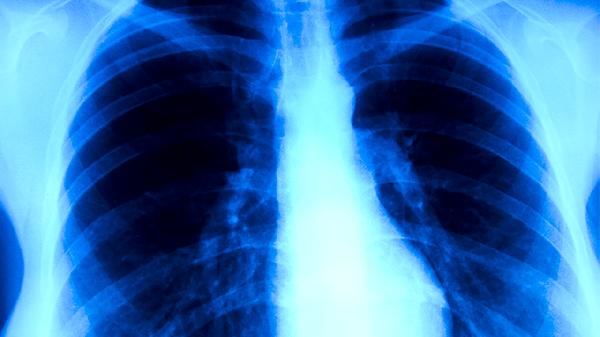

肺癌早期通常不會直接引起胃部不適,但可能因腫瘤壓迫、轉(zhuǎn)移或伴隨癥狀間接導(dǎo)致胃部不適。胃部不適可能與肺癌相關(guān)的因素包括腫瘤壓迫迷走神經(jīng)、化療藥物副作用、癌性惡病質(zhì)、心理壓力反應(yīng)、副腫瘤綜合征等。

肺部腫瘤生長至一定體積時可能壓迫迷走神經(jīng),該神經(jīng)支配部分消化道功能。神經(jīng)受壓后可出現(xiàn)胃蠕動異常,表現(xiàn)為上腹飽脹、惡心等癥狀。臨床需通過影像學(xué)檢查確認(rèn)腫瘤位置與神經(jīng)關(guān)系,解除壓迫是根本解決方式。